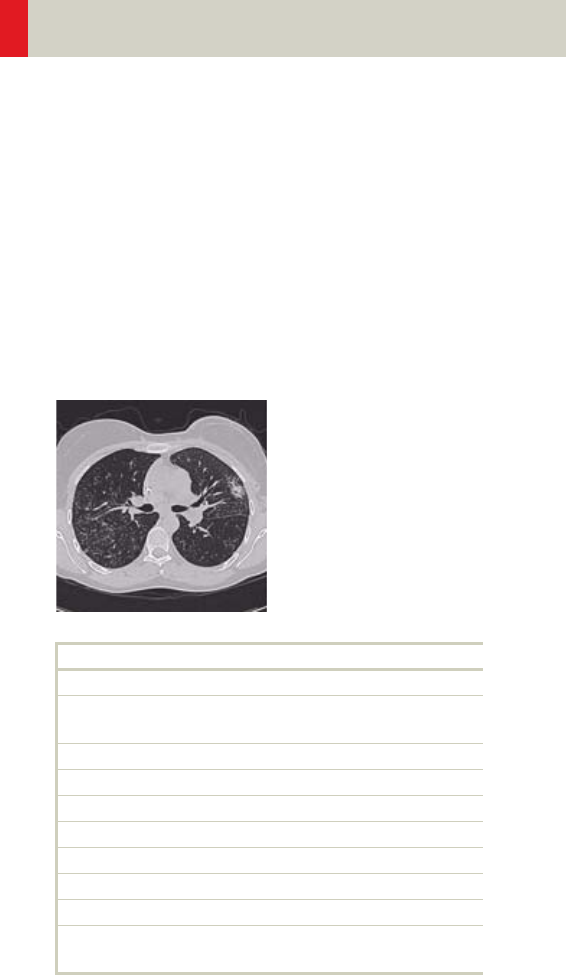

Thorax 226

- General Hints 229

- Body Kernels 231